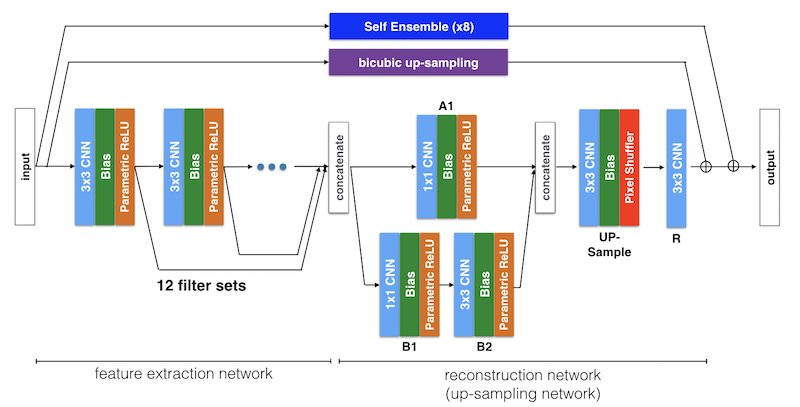

10.5、修改的SRResNet

In [36]

# cite: https://aistudio.baidu.com/aistudio/projectdetail/2884850?channelType=0&channel=0

import paddle

from paddle.fluid.layers.nn import transpose

import paddle.nn as nn

import math

import paddle.nn.functional as F

class simam_module(nn.Layer):

def __init__(self, channels, e_lambda = 1e-4):

super(simam_module, self).__init__()

self.activaton = nn.Sigmoid()

self.e_lambda = e_lambda

def __repr__(self):

s = self.__class__.__name__ + '('

s += ('lambda=%f)' % self.e_lambda)

return s

@staticmethod

def get_module_name():

return "simam"

def forward(self, x):

b, c, h, w = x.shape

n = w * h - 1

x_minus_mu_square = (x - x.mean(axis=[2,3], keepdim=True)).pow(2)

y = x_minus_mu_square / (4 * (x_minus_mu_square.sum(axis=[2,3], keepdim=True) / n + self.e_lambda)) + 0.5

return x * self.activaton(y)

# return x * y

if __name__ == '__main__':

x = paddle.randn(shape=[1, 16, 64, 64]) # b, c, h, w

simam = simam_module(16)

y = simam(x)

print(y.shape)[1, 16, 64, 64]

In [37]

class LayerNormFunction(P.autograd.PyLayer):

@staticmethod

def forward(ctx, x, weight, bias, eps):

ctx.eps = eps

N, C, H, W = x.shape[0],x.shape[1],x.shape[2],x.shape[3]

mu = x.mean(1, keepdim=True)

var = (x - mu).pow(2).mean(1, keepdim=True)

y = (x - mu) / (var + eps).sqrt()

ctx.save_for_backward(y, var, weight)

y = weight.reshape([1, C, 1, 1]) * y + bias.reshape([1, C, 1, 1])

return y

@staticmethod

def backward(ctx, grad_output):

eps = ctx.eps

N, C, H, W = grad_output.shape[0],grad_output.shape[1],grad_output.shape[2],grad_output.shape[3]

# y, var, weight = ctx.saved_variables

y, var, weight = ctx.saved_tensor()

g = grad_output * weight.reshape([1, C, 1, 1])

mean_g = g.mean(axis=1, keepdim=True)

mean_gy = (g * y).mean(axis=1, keepdim=True)

gx = 1. / P.sqrt(var + eps) * (g - y * mean_gy - mean_g)

return gx, (grad_output * y).sum(axis=3).sum(axis=2).sum(axis=0), grad_output.sum(axis=3).sum(axis=2).sum(

axis=0)In [38]

class LayerNorm2d(nn.Layer):

def __init__(self, channels, eps=1e-6):

super(LayerNorm2d, self).__init__()

weight = P.static.create_parameter([channels], dtype='float32')

bias = P.static.create_parameter([channels], dtype='float32')

self.add_parameter('weight',weight)

self.add_parameter('bias',bias)

self.eps = eps

def forward(self, x):

return LayerNormFunction.apply(x, self.weight, self.bias, self.eps)

mylayer = LayerNorm2d(2)

for name, param in mylayer.named_parameters():

print(name, param) # will print w_tmp,_linear.weight,_linear.biasweight Parameter containing:

Tensor(shape=[2], dtype=float32, place=Place(gpu:0), stop_gradient=False,

[-0.00963153, 0.00699809])

bias Parameter containing:

Tensor(shape=[2], dtype=float32, place=Place(gpu:0), stop_gradient=False,

[-0.02439881, 0.00256911])

In [39]

from paddle.nn import Layer

from paddle import nn

import math

# 是可以保持w,h不变的

class ConvolutionalBlock2(nn.Layer):

"""

卷积模块,由卷积层, BN归一化层, 激活层构成.

"""

def __init__(self, in_channels, out_channels, kernel_size, stride=1, batch_norm=False, activation=None):

"""

:参数 in_channels: 输入通道数

:参数 out_channels: 输出通道数

:参数 kernel_size: 核大小

:参数 stride: 步长

:参数 batch_norm: 是否包含BN层

:参数 activation: 激活层类型; 如果没有则为None

"""

super(ConvolutionalBlock2, self).__init__()

if activation is not None:

activation = activation.lower()

assert activation in {'prelu', 'leakyrelu', 'tanh'}

# 层列表

layers = list()

# 1个卷积层

layers.append(

nn.Conv2D(in_channels=in_channels, out_channels=out_channels, kernel_size=kernel_size, stride=stride,

padding=kernel_size // 2))

# 1个BN归一化层

if batch_norm is True:

# layers.append(nn.BatchNorm2D(num_features=out_channels))

layers.append(LayerNorm2d(out_channels)) # 添加了一个layernorm层 'psnr': 35.01214982299412, 'ssim': 0.9695686973520531

# 1个激活层

if activation == 'prelu':

layers.append(nn.PReLU())

elif activation == 'leakyrelu':

layers.append(nn.LeakyReLU(0.2))

elif activation == 'tanh':

layers.append(nn.Tanh())

# 合并层

self.conv_block = nn.Sequential(*layers)

def forward(self, input):

output = self.conv_block(input)

return output

# w,h放大

class SubPixelConvolutionalBlock2(nn.Layer):

def __init__(self, kernel_size=3, n_channels=64, scaling_factor=2):

super(SubPixelConvolutionalBlock2, self).__init__()

# 首先通过卷积将通道数扩展为 scaling factor^2 倍

self.conv = nn.Conv2D(in_channels=n_channels, out_channels=n_channels * (scaling_factor ** 2),

kernel_size=kernel_size, padding=kernel_size // 2)

# 进行像素清洗,合并相关通道数据 放大了图像

self.pixel_shuffle = nn.PixelShuffle(upscale_factor=scaling_factor)

# 最后添加激活层

self.prelu = nn.PReLU()

def forward(self, input):

output = self.conv(input)

output = self.pixel_shuffle(output)

output = self.prelu(output)

return output

class ResidualBlock2(nn.Layer):

"""

残差模块, 包含两个卷积模块和一个跳连.

"""

def __init__(self, kernel_size=3, n_channels=64):

"""

:参数 kernel_size: 核大小

:参数 n_channels: 输入和输出通道数(由于是ResNet网络,需要做跳连,因此输入和输出通道数是一致的)

"""

super(ResidualBlock2, self).__init__()

# 第一个卷积块

self.conv_block1 = ConvolutionalBlock2(in_channels=n_channels, out_channels=n_channels, kernel_size=kernel_size,

batch_norm=True, activation='PReLu')

# 第二个卷积块

self.conv_block2 = ConvolutionalBlock2(in_channels=n_channels, out_channels=n_channels, kernel_size=kernel_size,

batch_norm=True, activation='PReLu')

def forward(self, input):

"""

前向传播.

:参数 input: 输入图像集,张量表示,大小为 (N, n_channels, w, h)

:返回: 输出图像集,张量表示,大小为 (N, n_channels, w, h)

"""

residual = input # (N, n_channels, w, h)

output = self.conv_block1(input) # (N, n_channels, w, h)

output = output + residual

output = self.conv_block2(output) # (N, n_channels, w, h)

output = output + residual # (N, n_channels, w, h)

return output

class SimpleGate(nn.Layer):

def __init__(self):

super(SimpleGate, self).__init__()

def forward(self, x):

x1, x2 = x.chunk(2, axis=1)

# 在通道上拆分x为两个数据块

return x1 , x2

class SRResNet2(nn.Layer):

# SRResNet(scaling_factor=2)

def __init__(self, large_kernel_size=9, small_kernel_size=3, n_channels=64, n_blocks=16, scaling_factor=2):

"""

:参数 large_kernel_size: 第一层卷积和最后一层卷积核大小

:参数 small_kernel_size: 中间层卷积核大小

:参数 n_channels: 中间层通道数

:参数 n_blocks: 残差模块数

:参数 scaling_factor: 放大比例

"""

super(SRResNet2, self).__init__()

# 放大比例必须为 2、 4 或 8

scaling_factor = int(scaling_factor)

assert scaling_factor in {2, 4, 8}, "放大比例必须为 2、 4 或 8!"

self.sca = simam_module(n_channels // 2)

# SimpleGate

self.sg = SimpleGate()

# 第一个卷积块

self.conv_block1 = ConvolutionalBlock2(in_channels=1, out_channels=n_channels, kernel_size=large_kernel_size,

batch_norm=False, activation='PReLu')

# 一系列残差模块, 每个残差模块包含一个跳连接

self.residual_blocks = nn.Sequential(

*[ResidualBlock2(kernel_size=small_kernel_size, n_channels=n_channels) for i in range(n_blocks)])

# 第二个卷积块

self.conv_block2 = ConvolutionalBlock2(in_channels=n_channels, out_channels=n_channels,

kernel_size=small_kernel_size,

batch_norm=True, activation=None)

# 放大通过子像素卷积模块实现, 每个模块放大两倍 log2 2=1

n_subpixel_convolution_blocks = int(math.log2(scaling_factor))

self.subpixel_convolutional_blocks = nn.Sequential(

*[SubPixelConvolutionalBlock2(kernel_size=small_kernel_size, n_channels=n_channels, scaling_factor=2) for i

in range(n_subpixel_convolution_blocks)])

# 最后一个卷积模块

self.conv_block3 = ConvolutionalBlock2(in_channels=n_channels, out_channels=1, kernel_size=large_kernel_size,

batch_norm=False, activation='Tanh')

self.beta = P.create_parameter(shape=[1, n_channels, 1, 1], dtype='float32') # 加了这个 'psnr': 35.24633049966084, 'ssim': 0.9703385639920482

def forward(self, lr_imgs):

"""

:参数 lr_imgs: 低分辨率输入图像集, 张量表示,大小为 (N, 3, w, h)

:返回: 高分辨率输出图像集, 张量表示, 大小为 (N, 3, w * scaling factor, h * scaling factor)

"""

output = self.conv_block1(lr_imgs) # (16, 3, 24, 24)

residual = output # (16, 64, 24, 24)

output = self.residual_blocks(output) # (16, 64, 24, 24)

# 从这

x1 , x2 = self.sg(output)

x1 = self.sca(x1)

x2 = self.sca(x2)

output = paddle.concat((x1,x2),axis=1)

# 到这加了这个chunk 'psnr': 35.135550619006025, 'ssim': 0.9703396077881369

output = self.conv_block2(output) # (16, 64, 24, 24)

output = output + residual * self.beta # (16, 64, 24, 24)

output = self.subpixel_convolutional_blocks(output) # (16, 64, 24 * 2, 24 * 2)

sr_imgs = self.conv_block3(output) # (16, 3, 24 * 2, 24 * 2)

return sr_imgs

if __name__ == '__main__':

img_channel = 1

width = 64

net = SRResNet2()

inp = P.randn((1, 1, 120, 120),dtype='float32')

out = net(inp)

print('inp',inp.shape)

print('out',out.shape)inp [1, 1, 120, 120] out [1, 1, 240, 240]